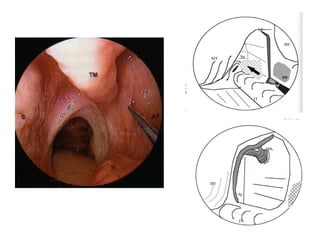

Schémas d’une embolisation d’anévrysme à l’aide de coils.

A. Cathétérisme du sac.

B. Vue finale après détachement du coil et retrait du microcathéter.

A B